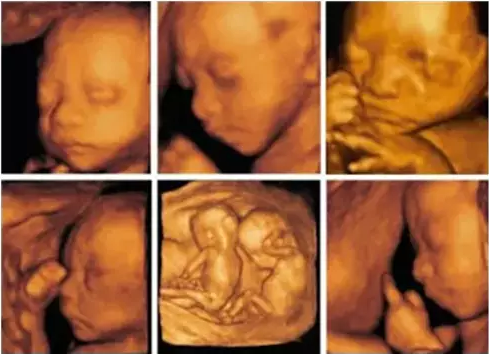

产前筛查,应该是先出现在脑海里的答案。随着超声技术的不断进步,四维彩超检查以立体动态成像、诊断全面准确等优于以往超声检查设备的功能和效果,逐渐成为产前筛查的重要手段。

但四维超声技术的发展并不止于此。全球医疗行业的积较引导者GE医疗集团推出的Voluson全系列超声诊断仪,每台诊断仪在早孕期检查、胎儿心脏评估、妇科疾病等方面都各有侧重。该系列诊断仪,以高于普通四维彩超设备的信号获取能力、传输速率和数据处理能力,增强了超声检查的穿透力、降低了运动伪像的干扰程度、缩短了检查成像时间,不仅能为产前筛查提供更精准的数据,还能对孕妇潜藏的各类疾病进行准确检测,确保母婴健康。